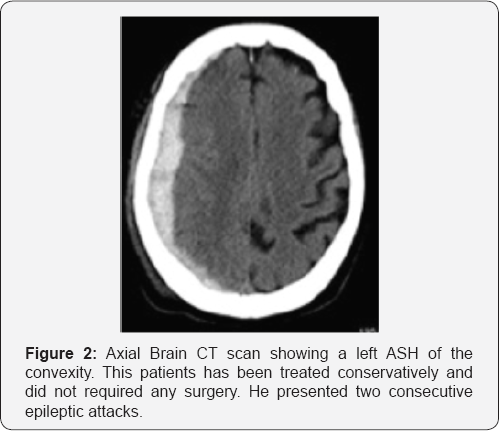

All 17 patients were initially treated conservatively. Three underwent an emergency craniotomy and evacuation of the ASH a few days after admission (range 24-56 hours), (Figure 1A & 1B) because of neurological deterioration and one patient died two days after admission for progressive increasing of the intracranial pressure. Among the rest of the patients treated medically (Figure 2) (13 patients) all out of two (11 patients) were transferred to a rehabilitation center or nursing home after a median of hospital staying of 23 days (range between 21 and 33 days). The other two were operated on for a chronic subdural hematoma (CSH) and a week postoperatively they were transferred back to the referring hospital. Also the three patients operated on for the ASH were transferred to a rehabilitation unit, just after a week from surgery. Among the 11 patients treated conservatively (Figure 2) and discharged from the neurosurgical ward, five (45%) were readmitted for the treatment of a developed CSH. All patients received IV steroids for a mean of 4 days (range 3-7) at the admission. In order to prevent thromboembolic events due to poor mobilization, we choose to start low molecular weight heparin (LMWH) 2 days after admission, but only in case the CT images were stable. All patients underwent a 12 hours post admission follow up CT scan or earlier in case of deterioration. A second scan was performed after 48-72 hours and then after a week and before the discharge as well as after 2, 4 and 6 weeks in order to detect the transformation from acute to CSH and any evidence of mass effect.

Among the 17 patients we tried to treat conservatively 1 died, 3 underwent an emergency craniotomy and evacuation of ASH. Thirteen were continuously treated conservatively. Among these, two patients were operated on for a CSH during the same in-hospital staying. One after 28 days and the other after 33 days from the trauma. Among the 11 patients discharged from the neurosurgical care, 5 were operated on for a CSH during a second admission and discharged back after a median time of 5 days; the remained 6 cases out of 17 (35,2%) were treated conservatively and at a median follow up of 11 months (range 8-14 months) they have a GOS between 2 and 5 (mean 3). At the same follow up the mean GOS for surgically treated patients was 2,9 (range 2-4).

Two out of three patients (66%) treated in the acute phase developed a urinary infection during hospitalization. Among patient treated conservatively (11 cases), seven developed urinary infection, other two pulmonary infection, one patients with an history of chronic atrial fibrillation went on to acute cardiac failure and 3 suffered from epileptic seizures. All these complications were treated successfully with antibiotics and medical treatment. Surgically treated patient underwent a median of 4 follow up CT scan (range 3-4) while conservative treated patients underwent a higher number of CT scans: a median of 6 (range 5-8). The overall mean hospitalization time was 24 days (range 14-38). The mean length of hospitalization after the surgical treatment was 10 days (range 7-12) while for conservative treated patients it was 26 days (range 24-33).